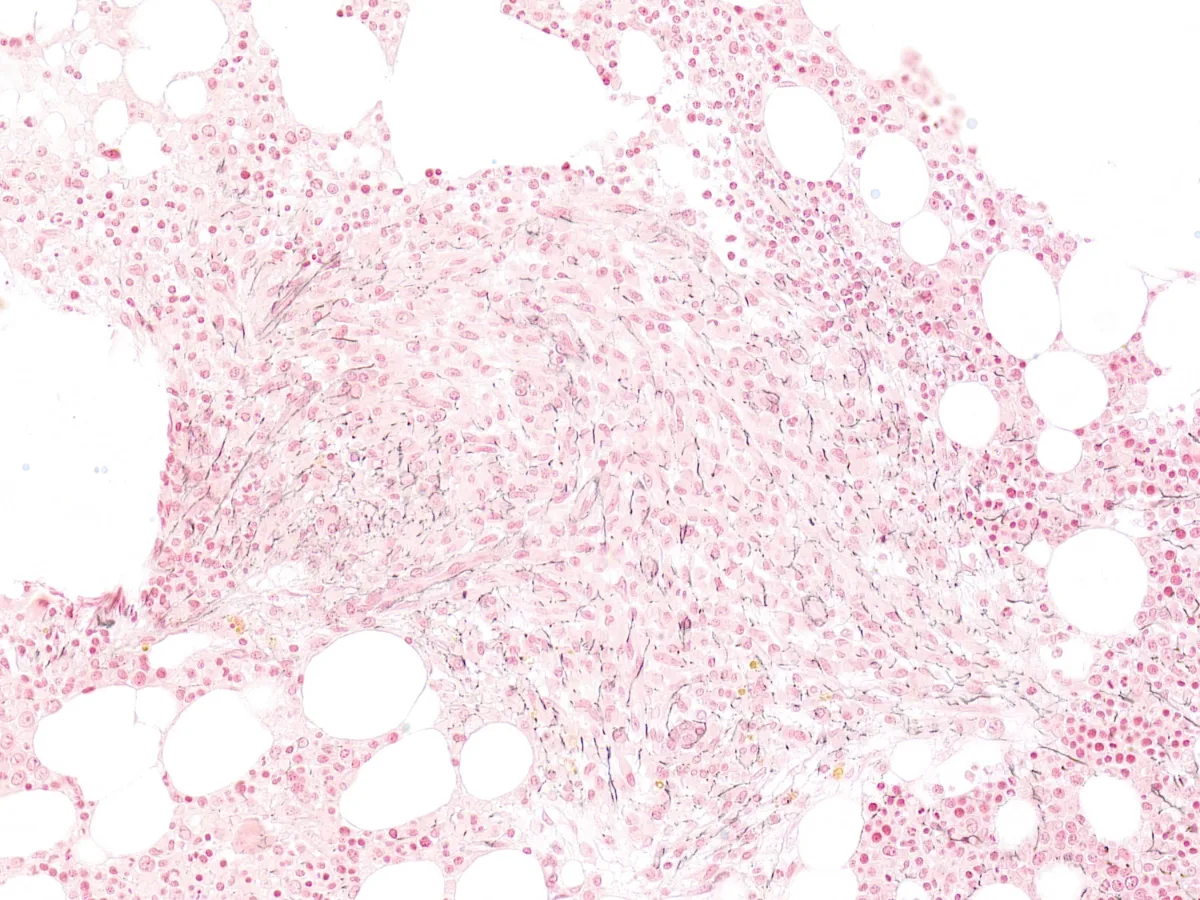

En el estudio de extensión se objetiva una Triptasa sérica elevada (181 µg/l), así como mutación en KIT p.D816V en sangre periférica. Se realiza biopsia de médula ósea…

Imágenes:

5. Triptasa 40x

Diagnóstico: Mastocitosis sistémica asociada a neoplasia hematológica (Policitemia Vera).

- Para el diagnóstico de mastocitosis sistémica (MS) es necesario el análisis citohistológico de una biopsia o aspirado de médula ósea, siendo el criterio mayor la presencia de agregados de >15 mastocitos en médula ósea u otros órganos extracutáneos y los criterios menores una morfología atípica, las mutaciones en KIT, una triptasa sérica elevada y un inmunofenotipo aberrante (incluyendo CD2, CD25 y CD30). PMID: 34901755

- La mastocitosis sistémica bien diferenciada (MSBD) representa un subtipo morfológico que puede verse en cualquier subtipo de MS, predominantemente en mujeres o en la infancia, con frecuente agregación familiar. Este subtipo morfológico presenta mastocitos de aspecto maduro y puede darse en cualquier subtipo de MS (presente en un 5% de los pacientes con MS). PMID: 26100086

- En la MSBD, el porcentaje de mastocitos en médula ósea es normalmente alto, con células redondas con núcleos centrados y gránulos citoplasmáticos. Los mastocitos suelen tener un fenotipo CD2-/débil, CD25-/débil y CD30+, y la mutación KITD816V es menos frecuente que en otros subtipos de MS. PMID: 26100086